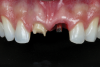

Fig 3. Intraoral view 3 months after implant installation.

Figure 3

After 3 months, when osseointegration was achieved, the definitive rehabilitation planning began (Figure 3). On the right central incisor, a fiber post was cemented and a build-up with composite resin was performed to facilitate placement of a complete ceramic crown. Upon completion of tooth preparation, polishing, and finishing, a vinyl polysiloxane impression was made of the implant abutment and tooth (Figure 4). The cast was scanned, and three pairs of crowns were fabricated using different materials and techniques: conventional zirconia veneered with feldspathic ceramic (Figure 5 through Figure 7), high-translucent monolithic zirconia (Figure 8 through Figure 10), and high-translucent monolithic zirconia minimally veneered just on the buccal side (Figure 11 through Figure 13).